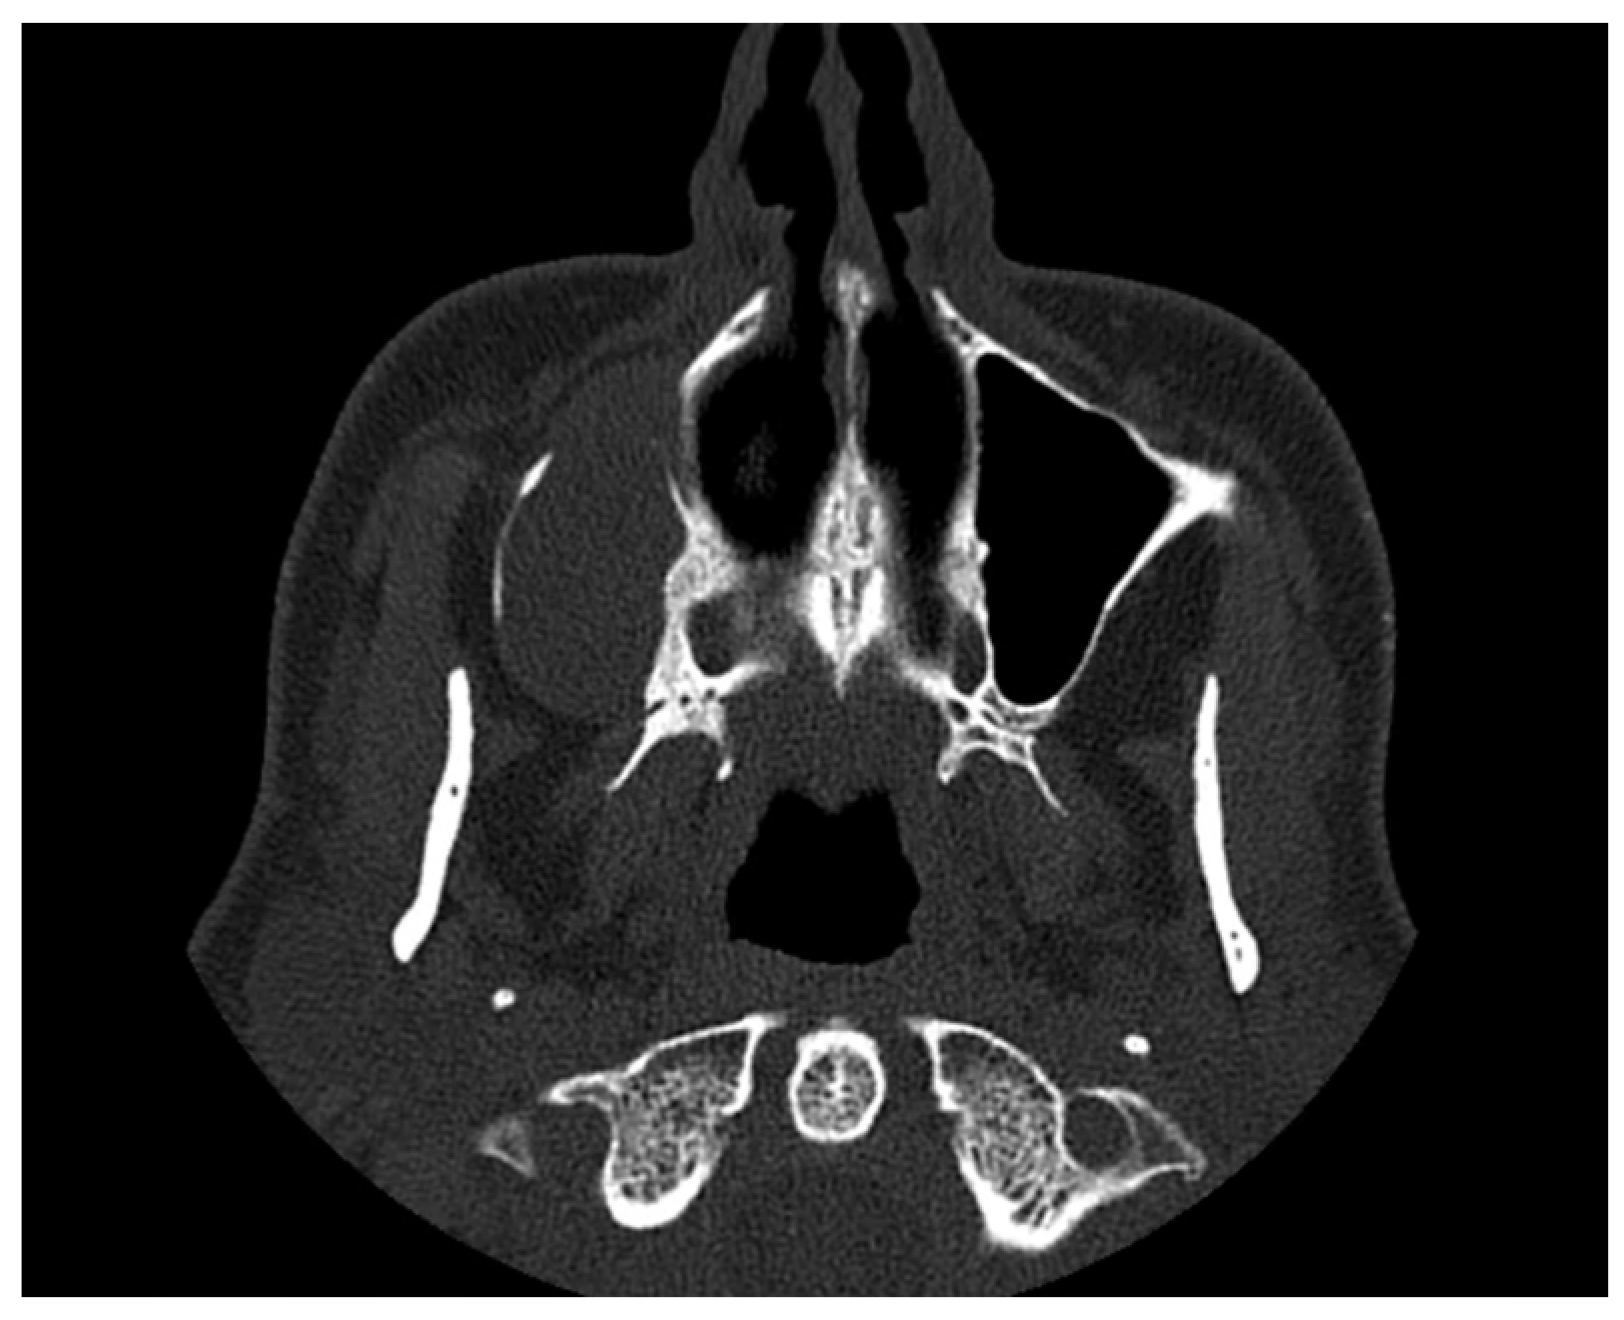

Concurrent Onset of Central Retinal Vein Occlusion and Inflammation of a Large Maxillary Odontogenic Cyst: Case Report and Analysis

2. Case Presentation